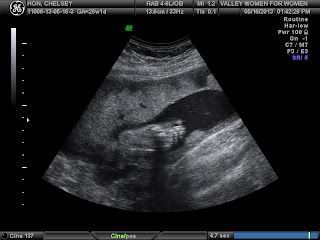

-Baby Girl Hon

The other person that has been making a lot of changes is our sweet baby girl! She is getting so big and so forceful in my tummy. She is causing some aches and pains but mainly we just love her to bits! I am finally in my third trimester and start going to the doctor every two weeks now. I have had two ultrasounds in the past two weeks, one at a college that a friend of mine did, and another at my actual doctor's office for a growth ultrasound. I have loved looking at this little girl so much lately. It's fun to actually be able to see what she is doing in there! At my ultrasound on Thursday we got lots of good pictures and I learned that she weighs 2 lb 9 oz. In just about 6 oz and about another inch, she will be as big as my baby cousin Ezra was when he was born. That's crazy!!! I love her so much though and I am really just ready, especially after getting a 3D shot of her face, to hold her and love her and take care of her.

Baby girl's Nose and lips :)

The little white fuzzy stuff on the left of her head is hair :) Already sprouting! No wonder I have had such terrible heartburn!

The left of the picture is her head, the right thing is her foot and toes. She is curled up in a tiny little ball!

Baby's foot. Look how cute and tiny it is!